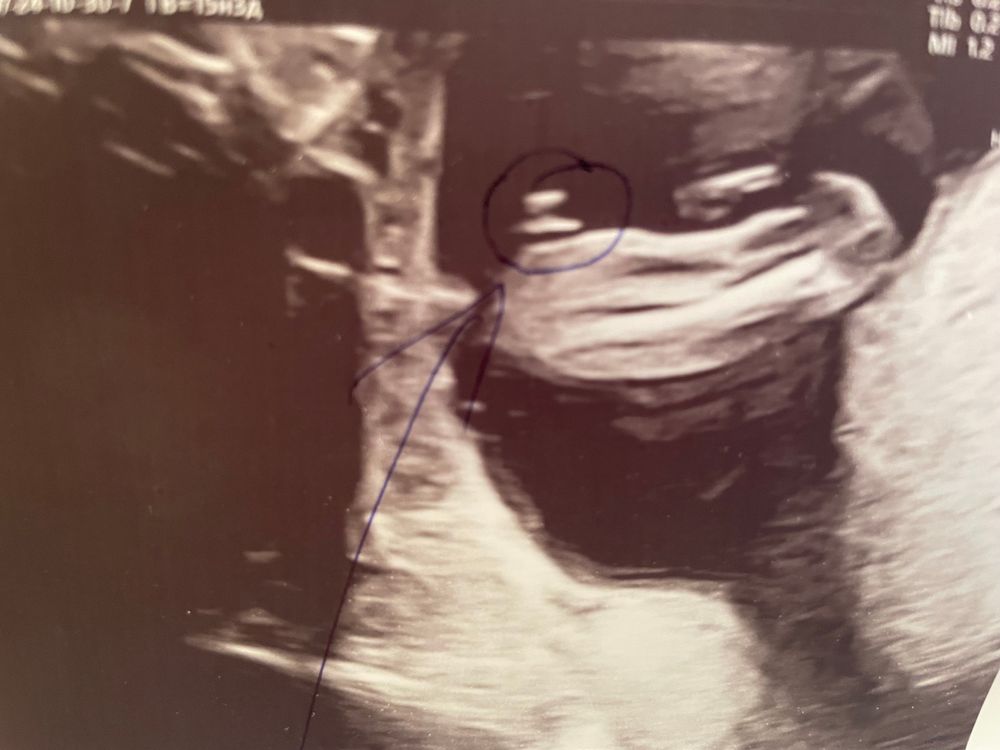

Девочка, если паралельно камешки

девочка, кофейное зёрнышко обведено и часть ножки. малышка сидит как бы на стеклянном столе полубоком, оперевшись на одну ножку, на фото вид снизу этого стола